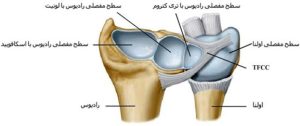

در فضای بین استخوان ساعد (رادیوس و اولنا ) و استخوان های مچ دست (لونیت و تریکوئتروم )فضای خالی وجود دارد ،در این فضا بافت مثلثی فیبری-غضروفی (TFCC) استخوان های ساعد را به استخوان های مچ دست متصل می کند. این ساختار که از رباطها ، تاندونها و غضروف ها تشکیل شده و حالت بالشتک مانندی دارد به قدرت و تثبیت مچ دست کمک می کند( شکل ۱).

این مجموعه پایدار کننده حرکات در تمام جهات مچ دست به اضافه حرکات چرخشی و تحت فشار می باشد.

شکل۱. در این شکل استخوان های رادیوس و اولنا و TFCC و اتصالات بین آنها نشان داده شده است.